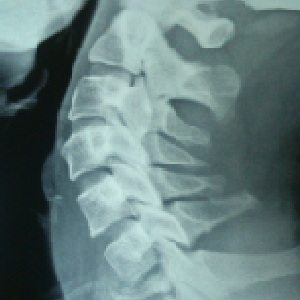

A very young pt of 25 years old, belonging to very good family, an engineer, had

tuberculosis of cervical

spine with destruction of C7 vertebra

if he would not get urgent attention and surgery, he could have landed up in developing

paraplegia

he was operated from front of the neck, a new vertebra(tricortical bone graft) was

put and fixed with plate

now he is doing very well in his life

Paeditric Koch’s - Spine